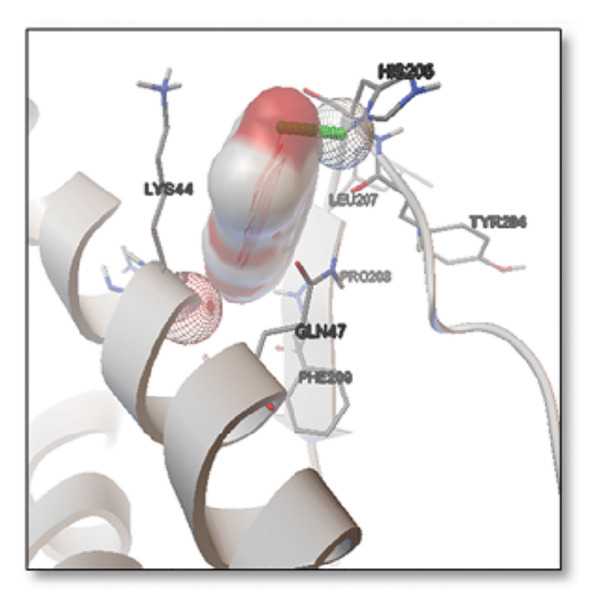

3.3. AutoDock Vina Results: Clusterin Receptor

Ginkgolide showed the strongest binding at −13.98 kcal/mol, interacting with HIS205. Other potent ligands were ginsenosides (−8.02 kcal/mol), which formed contacts with PHE240, and berberine (−6.46 kcal/mol), interacting with ASN291. Resveratrol also exhibited favorable binding (−6.34 kcal/mol), forming H‐bonds with PRO212 and ALA373. Cannabidiol had the weakest binding at −3.56 kcal/mol, interacting with ARG292:HE1. The weakest binder was cyanidin (−3.92 kcal/mol), which showed no hydrogen bond interactions.

For reference drugs, donepezil (−5.65 kcal/mol) with GLY378, Figure 3 illustrates the binding characteristics of natural ligands and reference drugs for the clusterin receptor.

The in silico predictions for ginkgolide’s interactions with sortilin, clusterin, and tau are well‐supported by the established structural and functional mechanisms of these proteins in scientific literature. For sortilin, the predicted interaction with ARG292 and TYR318 is consistent with the protein’s known structure. Studies have shown that its large, ten‐bladed β‐propeller domain is the primary ligand‐binding site; ARG292, often positioned near the VPS10P domain, likely provides critical electrostatic stabilization, while TYR318 contributes $\pi‐\pi$ or $\pi$‐cation interactions, collectively stabilizing the ligand–receptor complex. This binding site overlaps with regions known to undergo conformational change during ligand recognition, suggesting ginkgolide may allosterically modulate the receptor’s trafficking function. A 2017 study by [ref. 38], for example, demonstrated how conformational changes in this domain, caused by pH, disrupt binding sites. Similarly, a review by Quistgaard et al. [ref. 39] highlights how the architecture of the VPS10 domain, which includes these residues, is vital for its function. For clusterin, the predicted interaction with HIS205 is supported by the protein’s established role as a molecular chaperone that prevents protein aggregation.

Histidine residues are frequently involved in coordinating chaperone‐substrate interactions. The binding of ginkgolide at HIS205 suggests it may stabilize the active conformation of the chaperone, thereby enhancing its ability to bind to and inhibit the formation of amyloid fibrils, a key mechanism reinforced by recent research published [ref. 40]. This research has consistently reinforced that clusterin’s ability to bind to and inhibit the formation of amyloid fibrils is a key mechanism of action, particularly in neurodegenerative diseases. While direct mention of HIS205 is rare, its chaperone function is broadly understood to rely on such key residues. Elias et al. [ref. 41] and Carini et al. [ref. 42] confirm that clusterin’s role in inhibiting aggregation is a major focus of current research. Finally, the predicted binding to HIS329 in tau is highly significant and directly corroborated by recent literature. HIS329 is explicitly located within the microtubule‐binding repeat domain, which is the primary site for tau’s pathological self‐aggregation. Ginkgolide’s predicted binding at this position is a direct mechanism of aggregation inhibition, suggesting it acts as a steric wedge or “capping agent” to prevent the formation of toxic beta sheet structures, aligning with similar strategies explored. Studies have explicitly identified histidine residues within the microtubule‐binding repeat domain as participants in tau’s self‐aggregation process. Hernández et al. [ref. 43] specifically names residues like H329 as being involved in this mechanism. Molecular docking and simulation studies, such as one from 2025 by Saha and Natarajan [ref. 44], also focus on targeting this domain with small molecules to inhibit tau pathology, providing strong support for the in silico predictions.